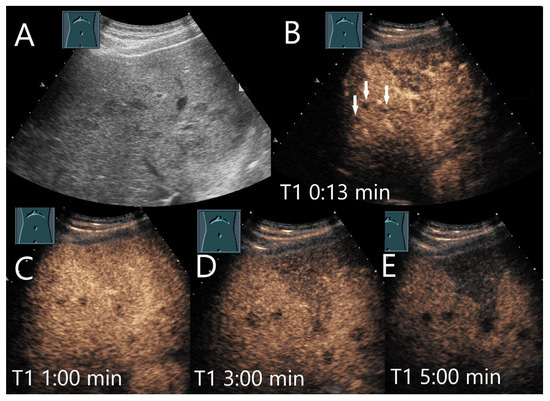

Figure 3.

Cavernous hemangioma. Female patient. Incidental finding of a 40 × 32 mm heterogeneous hypoechoic FLL (A). The CEUS shows arterial marginal hyperenhancement after 14 s (B) and homogeneous AP hyperenhancement after 1:00 min (C). Decreasing heterogeneous hyperenhancement after 2:16 min (D) and 3:07 min (E). After 4:30 min (F), there is a clear hypoenhancement. Clinical ultrasound revealed the diagnosis of a hemangioma. Histologically, a cavernous hemangioma was confirmed.